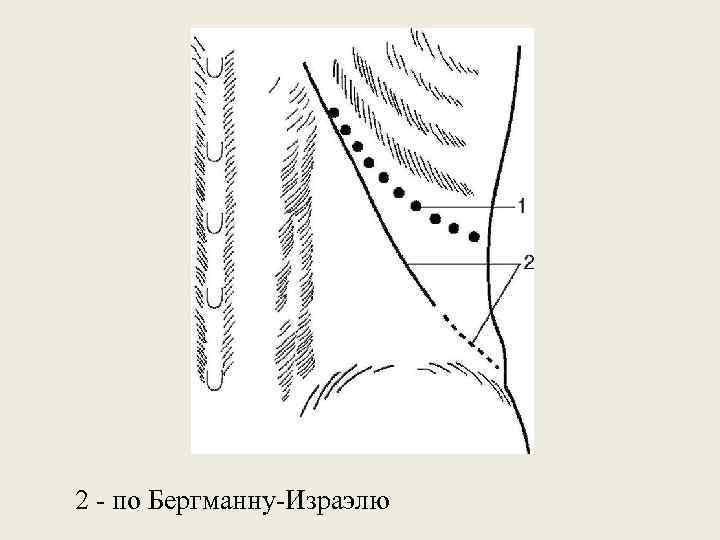

2 - по Бергманну-Израэлю